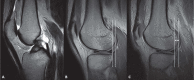

Standard knee imaging with MRI is usually performed with patient in recumbent position under non-weight-bearing conditions. Recently, magnetic resonance imaging systems to scan the knee joint under weight bearing conditions has been proposed as an approach to improve the clinical utility of musculoskeletal MRI. Imaging under loading can be useful to understand the natural motion behavior of the knee joint and to identify conditions that are challenging to diagnose by using standard position. We reviewed the literature on weight-bearing MR imaging of the knee to describe the current state of use of such MRI technologies, evaluating the advantages and the potential limitations of these technologies.